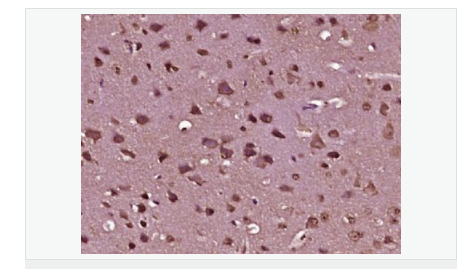

image.png